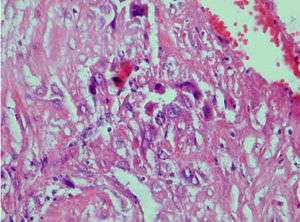

Photomicrograph showing proliferating intermediate trophoblast with scarce cytotophoblastic and systrophoblastic elements

Placental Site Trophoblastic Tumor is a monophasic neoplasm of the implantation site intermediate trophoblast, and usually a benign lesion, which comprises less than 2% of all gestational trophoblastic proliferations. Preceding conditions include molar pregnancy(5%). Compared to choriocarcinoma or invasive mole, hemorrhage is less conspicuous and serum β-HCG level is low, making early diagnosis difficult.

Immunohistochemistry: Often stains with hPL, keratin, Mel-CAM, EGFR.